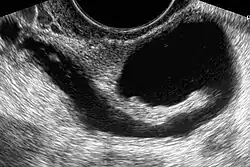

Die Diagnose kann mit Hilfe verschiedener bildgebender Verfahren gestellt werden: mit der Hystero-Kontrast-Salpingographie, mittels Computertomographie, heute mittels Magnetresonanztomographie oder als Methode der Wahl durch die Sonographie.[2][8][3][9]